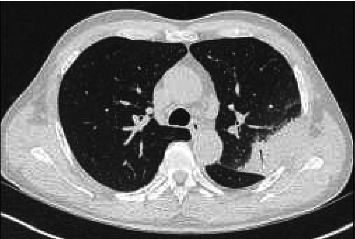

Chlamydia psittaci, the causative agent of psittacosis, is an intracellular bacterium typically transmitted from birds to humans, leading to atypical pneumonia. We present a case of a 60-year-old man with no reported bird exposure but a history of working as a chief cook, potentially exposed to poultry. He presented with high fever, diffuse soreness, and left-sided pulmonary consolidation. Initial treatment with β-lactams was ineffective, but a multiplex PCR on bronchoalveolar lavage identified C. psittaci DNA. Therapy was switched to moxifloxacin, resulting in rapid clinical improvement. C. psittaci causes approximately 1% of community-acquired pneumonias, often underdiagnosed due to nonspecific symptoms and the need for advanced diagnostic tools like nucleic acid amplification tests (NAATs) or metagenomic next-generation sequencing (mNGS). The bacterium is endemic in birds and poultry, with human infections linked to occupational exposure or contact with infected animals. Diagnosis relies on NAAT and mNGS, as serology and culture are less practical. Treatment with tetracyclines, quinolones, or macrolides is effective, reducing mortality from 10%-20% to < 1%. Preventive measures, including protective equipment for high-risk individuals and treatment of infected birds, are crucial. Mandatory reporting of cases could improve understanding of the disease burden. This case highlights the importance of considering psittacosis in atypical pneumonia, even without direct bird exposure, and the role of NAAT or mNGS in accurate diagnosis.

Abstract Image